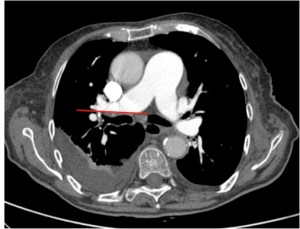

Cono de la pulmonar de calibre aumentado.

Cono de la pulmonar de calibre aumentado, indicativo de hipertensión pulmonar radiológica.

Relación VI/VD > 1. Signo de muy mal pronóstico.

Relación VI/VD > 1. El tabique interventricular está empezando a desviarse hacia el VI. Signos de muy mal pronóstico.

TEP agudo en silla de montar, el trombo se extiende desde una arteria pulmonar a la otra.